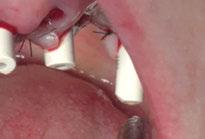

y lo que se pudo preservar del hueso malar. Se añadió una malla sinterizada infraorbitaria para dar volumen a la mejilla y se planificaron dos brazos de conexión que emergieran en las posiciones 24 y 26 de forma subgingival (Figuras 8 y 9). La superficie interna que apoyaba en el hueso era de titanio microrrugoso, y la superficie externa y conectores de titanio pulido y hexágono externo universal (Figuras 10 y 11). La cirugía se hizo bajo anestesia general en infiltración con anestesia local (4% articaína, 1:100.00 epinefrina), levantando el

colgajo cutáneo de la mejilla por vía intraoral, preservando el colgajo temporal para no comunicar con el remanente de la cavidad naso maxilar (Figura 12). Se emplearon 10 tornillos de osteosíntesis de 1,9 mm y la estabilidad primaria obtenida fue excelente (Figura 13)

4 meses después de la cirugía la encía estaba completamente cicatrizada y las conexiones de los implantes tipo hexágono externo universal quedaron a nivel yuxtamucoso. En este caso no se requirió el empleo de pilares transepiteliales y las impresiones fueron tomadas

Figura 13. Fijación del implante y emergencia de las conexiones.